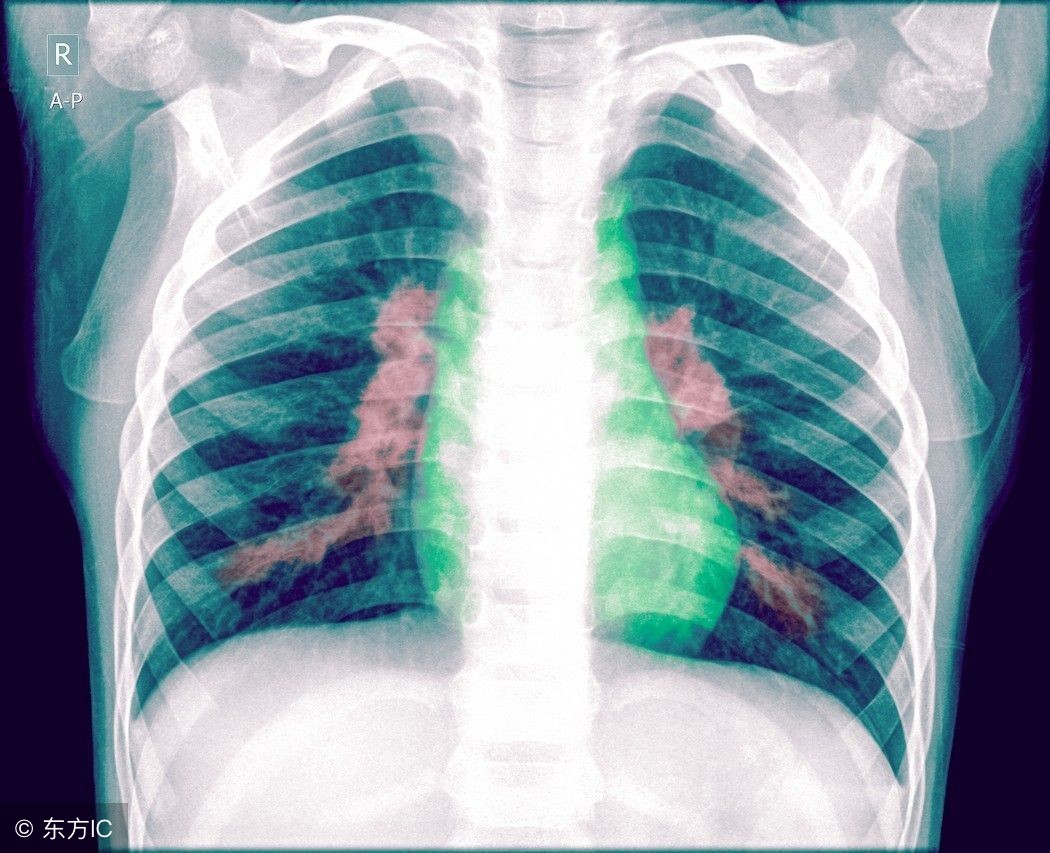

肺炎疾病是人们生活中常见而不陌生的了。要是人们患上肺炎疾病的刹那是很担心的,肺炎患者的饮食是会受限制的。不同的致病原可引起不同类型的肺炎。那么,如何鉴定宝宝得了肺炎呢?